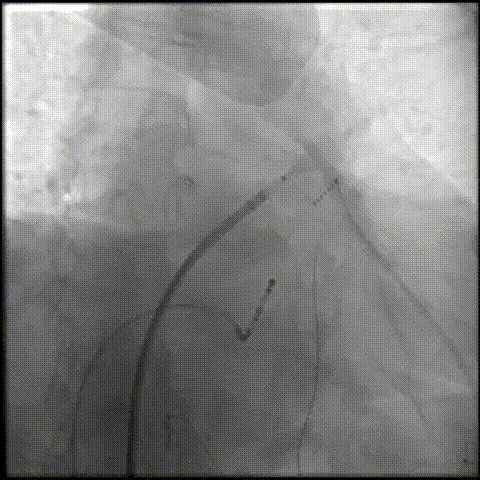

LAMax LAAC® 2430 Normal封堵器封堵盘在DSA下牵拉15s,锚定伞稳定无移位。

牵拉实验

打开封堵伞造影